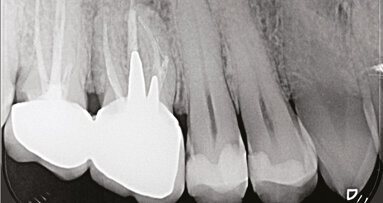

Tuttavia, queste metodiche permettono solamente la visualizzazione bidimensionale delle strutture esaminate e hanno comunque delle limitazioni per chi deve fare misurazioni: ingrandimento, distorsione, sovrapposizioni delle strutture anatomiche esaminate e false immagini. Errori d’identificazione e una ridotta precisione nelle misurazioni morfologiche o cefalometriche possono portare a una diagnosi errata, soprattutto in ortognatodonzia.

La TAC Cone Beam (CBCT) rappresenta sicuramente un’importante innovazione nel campo dei sistemi di acquisizione tomografici e delle ricostruzioni volumetriche. Inizialmente applicata in angiografia e in radioterapia, la tecnologia Cone Beam CT ha trovato negli anni recenti un forte sviluppo in ambito odontoiatrico. Specialmente con la messa a punto di software specifici per la ricostruzione 3D e hardware in grado di gestire la mole di dati da elaborare, ha permesso una riduzione dei costi di acquisto delle apparecchiature e una conseguente maggiore diffusione. La CBCT applicata al campo dentale ha dato il via a dei sistemi dedicati, avendo come risultato un’aumentata qualità dell’imaging con una notevole riduzione della dose di radiazioni data al paziente, tale da poterla usare anche nei bambini con particolari patologie. Infatti, la Cone Beam, a confronto delle TC più moderne, presenta dosi da 3 a 10 volte inferiori a parità di volume irradiato. Il sistema CBCT permette la creazione di immagini su tutti i piani nello spazio (assiale, coronale, sagittale, obliquo) o addirittura ricostruzioni seguendo una linea curva attraverso un processo denominato “Multi Planar Reconstruction” (MPR). Gli apparecchi radiologici Cone Beam emettono fasci di raggi X che hanno la forma conica, anziché a ventaglio come gli apparecchi usati per la tomografia computerizzata convenzionale (CT o MSCT). L’esposizione è a radiazioni pulsate e permette di acquisire le immagini base con un’unica rotazione per tutto il FOV (field of view) selezionato. Successivamente, è possibile tramite software elaborare i dati acquisiti trasformandoli in un unico volume il cui elemento essenziale è il voxel (pixel 3D). Più piccolo è il voxel più è definita l’immagine Cone Beam. Da questo volume si possono ricalcolare tutte le immagini volute con l’orientamento a scelta senza distorsioni; i voxel, infatti, sono isotropici (di ugual misura nelle tre dimensioni dello spazio).

I vantaggi della CBCT in ambito diagnostico sono sicuramente molti: valutazione 3D dell’osso alveolare e strutture anatomiche adiacenti (nervi e vasi) per la pianificazione del posizionamento degli impianti e mini-viti; inclinazione e torque radicolare reale; posizione tridimensionale degli elementi inclusi e sovrannumerari; riassorbimenti radicolari; relazioni dei tessuti molli; dimensione e posizione della lingua; valutazione 3D delle vie aeree, dell’articolazione temporo-mandibolare e dei pazienti ortodontico-chirurgici, sindromici o con schisi; studio cefalometrico tridimensionale e delle vertebre cervicali per valutazioni axulogiche e posturali.

Gli svantaggi, invece, della CBCT in ambito diagnostico possono essere: una curva d’apprendimento dei medici, odontoiatri e ortodontisti; una dotazione informatica adeguata e aggiornata; la paura di un’esposizione del paziente a un dosaggio di radiazioni eccessive; una troppo rapida evoluzione tecnologica; il problema d’ingombro della macchina; la radiazione dispersa. Risulta difficile poter definire dei reali svantaggi nel confronto con le potenzialità offerte da questa nuova tecnica di imaging, tuttavia esistono degli aspetti gestionali che attualmente frenano la diffusione di tali apparecchiature. Se escludiamo la TAC multislice, appare evidente che lo status radiografico esponga a una radiazione spropositata rispetto al risultato diagnostico ottenuto (150 μSv), mentre i dosaggi delle varie TAC volumetriche appaiono più che accettabili, soprattutto nella considerazione che da un volume cranico completo è possibile estrarre l’immagine laterolaterale, l’antero-posteriore, l’assiale e la panoramica. Considerando la sommatoria di tale irraggiamento con tecnica analogica, si passano sicuramente i 60 μSv (CBCT 50-110 μSv, MSCT 2000-3300 μSv) . Si evince, quindi, che la paura di esporre il paziente a dosaggi eccessivi sembra non essere supportata da evidenze scientifiche. Allo stato attuale della tecnologia per un paziente ortodontico senza particolari sospetti malformativi, le indagini radiologiche che seguono il principio ALARA dovrebbero prevedere teleradiografia e panoramica digitali ma, nel caso in cui necessiti ulteriori o particolari informazioni, la radiologia volumetrica di tutto il cranio effettuata con apparecchi di ultima generazione è senz’altro la scelta più conveniente in rapporto al dosaggio.